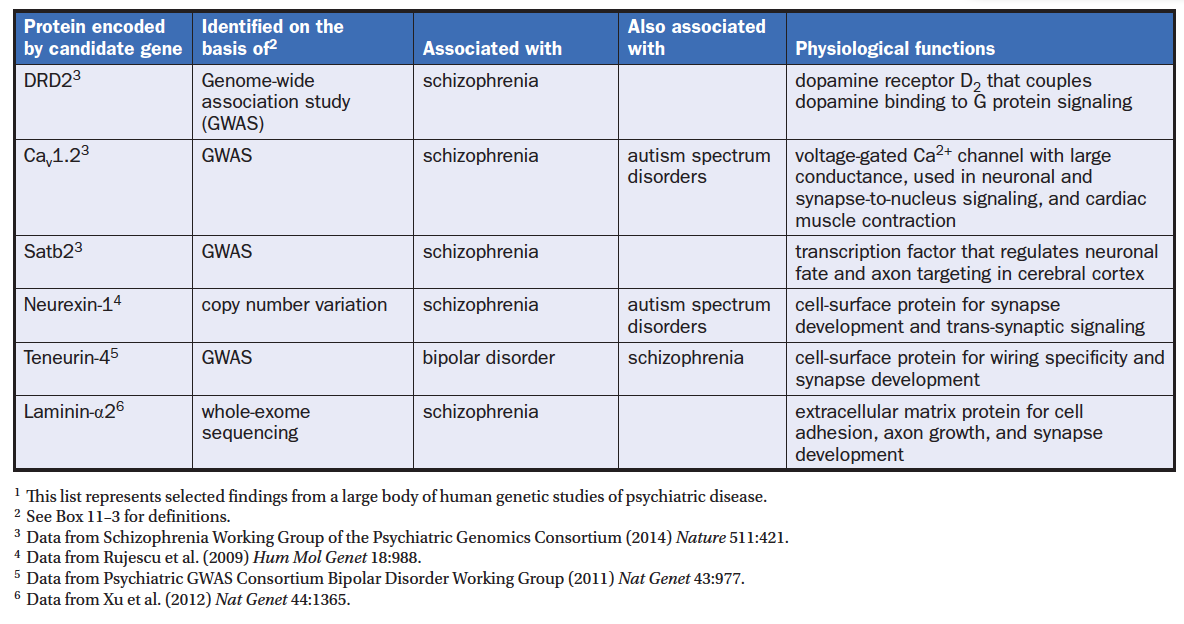

Candidate genes associated with psychiatric disorders

- Schizophrenia and bipolar disorder are heritable (80%)

- Depression and anxiety disorders is lower (30%)

- No simple Mendelian inheritance pattern has been shown but many genes have been implicated to be risk factors

Note:

Table 11-2 Selected candidate genes associated with psychiatric disorders.